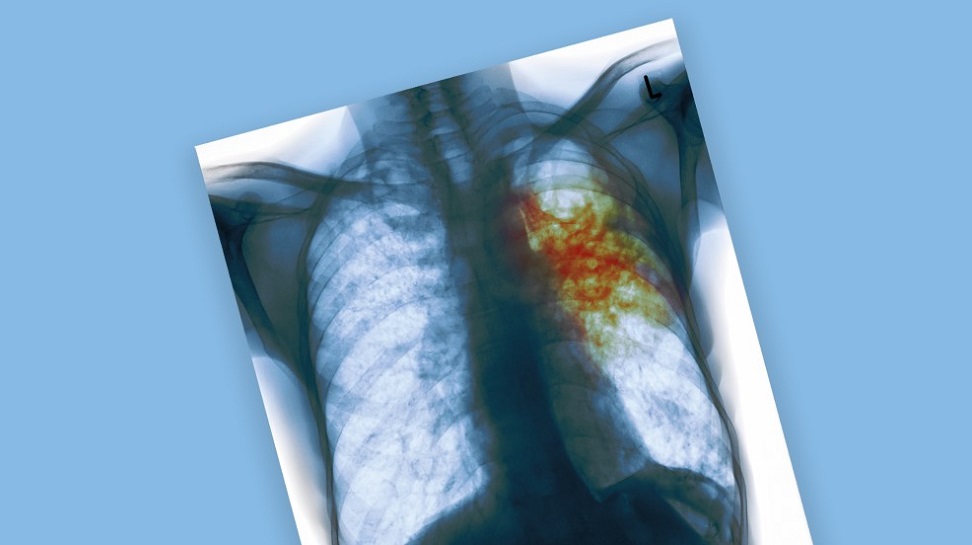

Всемирный день борьбы с туберкулёзом

Опубликовано: 23.03.2022Диагностика туберкулеза у детей. Вопросы и ответы

Туберкулёз – инфекционная болезнь, которую вызывают микобактерии туберкулёза. Наиболее часто при туберкулёзе поражаются лёгкие. Иногда туберкулёз называют социальной болезнью, поскольку она часто встречается у людей с низким уровнем жизни, испытывающих стресс и лишения в повседневной жизни. Однако, несмотря на правильность этого тезиса, заболеть туберкулёзом может абсолютно каждый – ведь все мы контактируем с внешним миром, а микобактерии все равно, где жить.

Туберкулёз

Туберкулёз – широко распространенное инфекционное заболевание, вызываемое микобактериями. Возбудитель туберкулёза – бактерия Mycobacterium tuberculosis. Она устойчива во внешней среде и в некоторых случаях способна сохраняться в высушенном виде годами. Источник инфекции – больные активной формой туберкулёза люди.